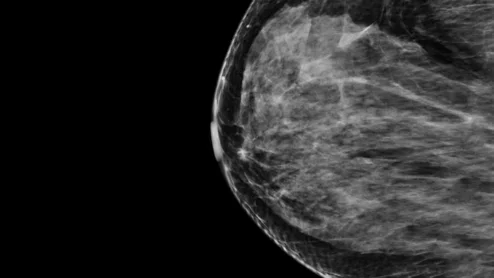

The technology is said to be twice as accurate at predicting five-year cancer risk compared to current risk assessment methods.

Thanks to AI, clinicians can use mammograms to do a lot more than identify signs of breast cancer. Researchers explored data from nearly 50,000 patients, presenting their findings in Heart.